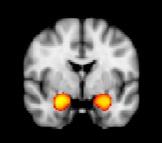

The team found that study participants with ASD and SOR had stronger brain responses to the sensory stimuli in brain areas that process sensory information, the primary somatosensory and auditory cortices, as well as in the amygdala, one of the brain's emotional centers. The brain responses were even more severe when participants with ASD and SOR were exposed simultaneously to the auditory and tactile stimuli. They also found that all study participants showed a similar initial brain response to the stimuli, but youth with ASD and SOR were much slower in getting used to the stimuli -- and reducing their brain response -- than were children with ASD but not SOR.

Green said that youth with ASD but not SOR may be compensating through strong brain connectivity between their prefrontal cortex and amygdala, an area involved in attention, response to threat and emotional reactions. The prefrontal cortex, Green said, is helping to regulate the strong response of the amygdala.